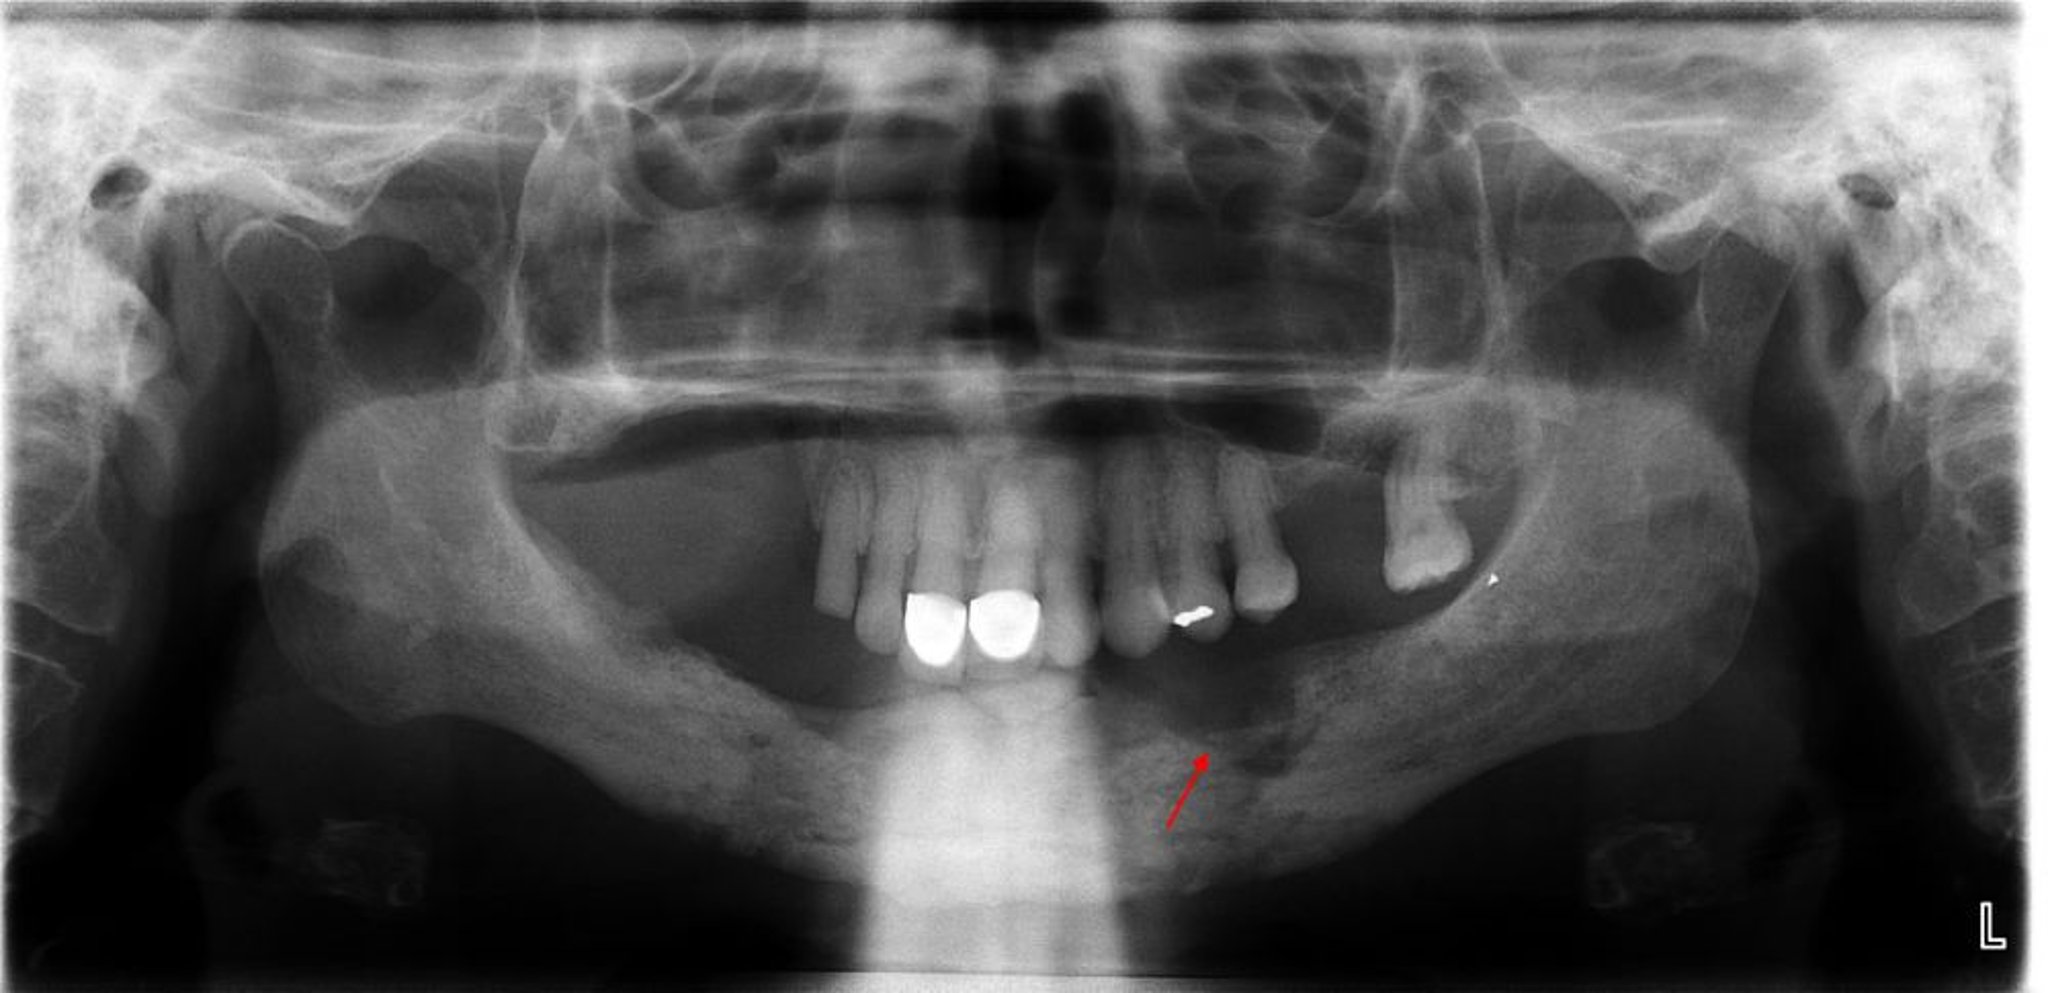

Viêm xương tủy

Phim chụp X-quang này cho thấy tình trạng viêm tủy xương với xương gãy rõ ràng (xương không còn sống) ở góc hàm dưới bên trái (mũi tên).

Hình ảnh do thạc sĩ, bác sĩ nha khoa Byron (Pete) Benson, Đại học Texas A&M, Cao đẳng Nha khoa Baylor cung cấp.